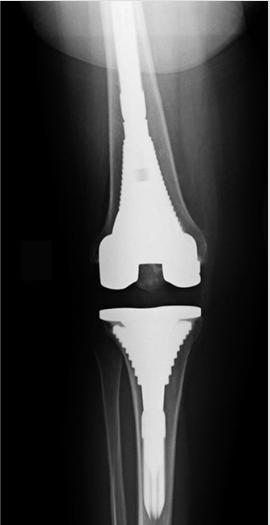

The revision knee replacement surgery involves repairing the damaged parts and removing and replacing a total or partial knee implant (prosthesis) with a new one.

Reasons leading to Revision Knee Replacement

• Replace a failed knee replacement device.

• To correct injury caused to the knee from side effects of the device.

• Loosening and wear of the implant

• Infection

• Bone grafts